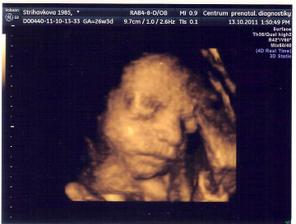

13.10.11 4D ve 27.týdnu

13.10.2011 Dle dnesniho 4D ma Emis 922g, kolik cm jsme se nedozvedeli, pry se to ted urcuje spatne.. Jinak to vypada, ze nosanek bude mit po tatinkovi a pusinku po mamince;) Moc se ji hybat nechtelo, spinkala, obcas se pohla, dala rucicky pred oblicej, nozku pres nozku a taky se usmala🙂)